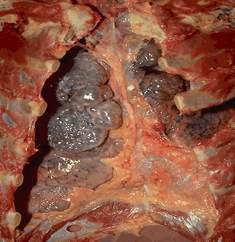

肉眼观,气肿肺明显膨胀,边缘变钝,表面可见肋骨压痕,肺组织柔软而缺乏弹性,色灰白,切面肺组织呈蜂窝状,触之捻发音增强。

图2-8